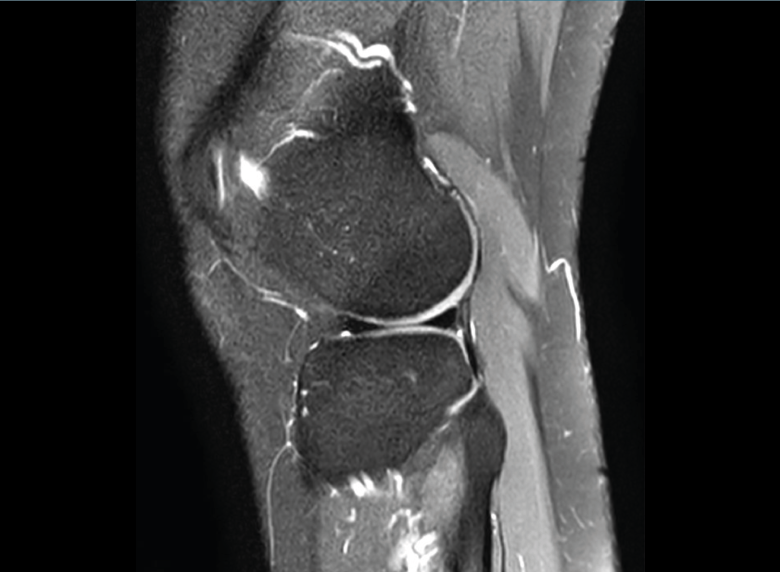

1.1. Meniscos

Se identifican como estructuras hipointensas en todas las secuencias, con asta anterior y posterior de morfología triangular.

La RM es la técnica de elección en el diagnóstico de la patología meniscal(17)(Figuras 30, 31, 32, 33, 34 y 35).

Figura 32. Corte de secuencia coronal T2 Fat-Sat de resonancia magnética de rodilla: rotura de menisco interno horizontal.

Figura 33. Corte de secuencia sagital T2 Fat-Sat de resonancia magnética de rodilla: menisco interno con cambios mucoides.

Figura 34. Corte de secuencia sagital T2 Fat-Sat de resonancia magnética de rodilla: rotura en asa de cubo desplazada al asta anterior del menisco externo.

Figura 35. Corte de secuencia coronal y sagital de resonancia magnética de rodilla: rotura en asa de cubo del menisco interno con fragmento desplazado al intercóndilo.

1.2. Ligamentos